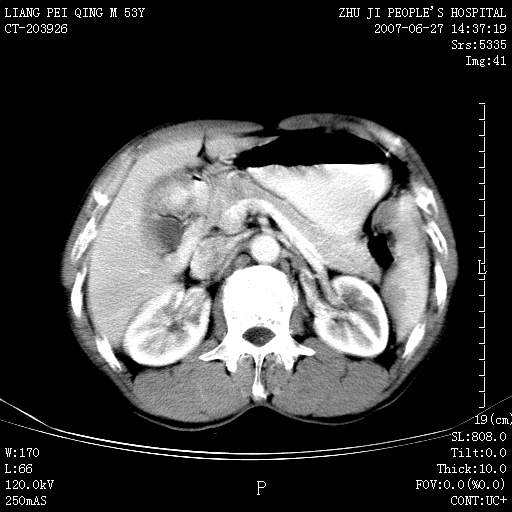

以下是引用余辉在2007-6-27 18:46:00的发言:[br]病灶多发,内可见大片状低密度区,病灶病灶等密度区轻度强化,动脉期后期病灶低密度区与高密度区对度增加,考虑1淋巴瘤2转移瘤3血管内皮细胞瘤(不知有否静脉期及延迟期扫描)

以下是引用zzzzhhhhaaaannnn在2007-6-27 20:44:00的发言:[br]脾脏 肋骨转移可能性大,下腔静脉内有癌栓

以下是引用狙击手在2007-6-28 10:35:00的发言:[br]1:定位:来源于脾脏。2:强化:强化,但不均匀。3:下腔静脉癌栓?下腔静脉充填不均匀与增强时间有关,延时即可明确。4:肋骨破坏?看起来并不确切。综上考虑几个最常见诊断:1;淋巴管瘤;2;血管内皮肉瘤(高度恶性,早期即可转移,常见肝,肺,骨)3;转移瘤(无特征性,只有肝或其它腹腔脏器有类似病变时,才可提示之)